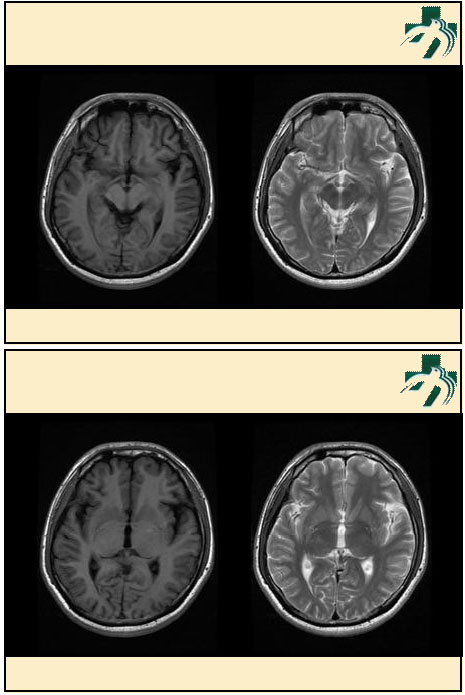

奴卡氏菌感染

第九期三博

读片会

病例之四

北京协和医院 提供

男性,22岁。自觉虫咬后皮疹、肢体麻木4月